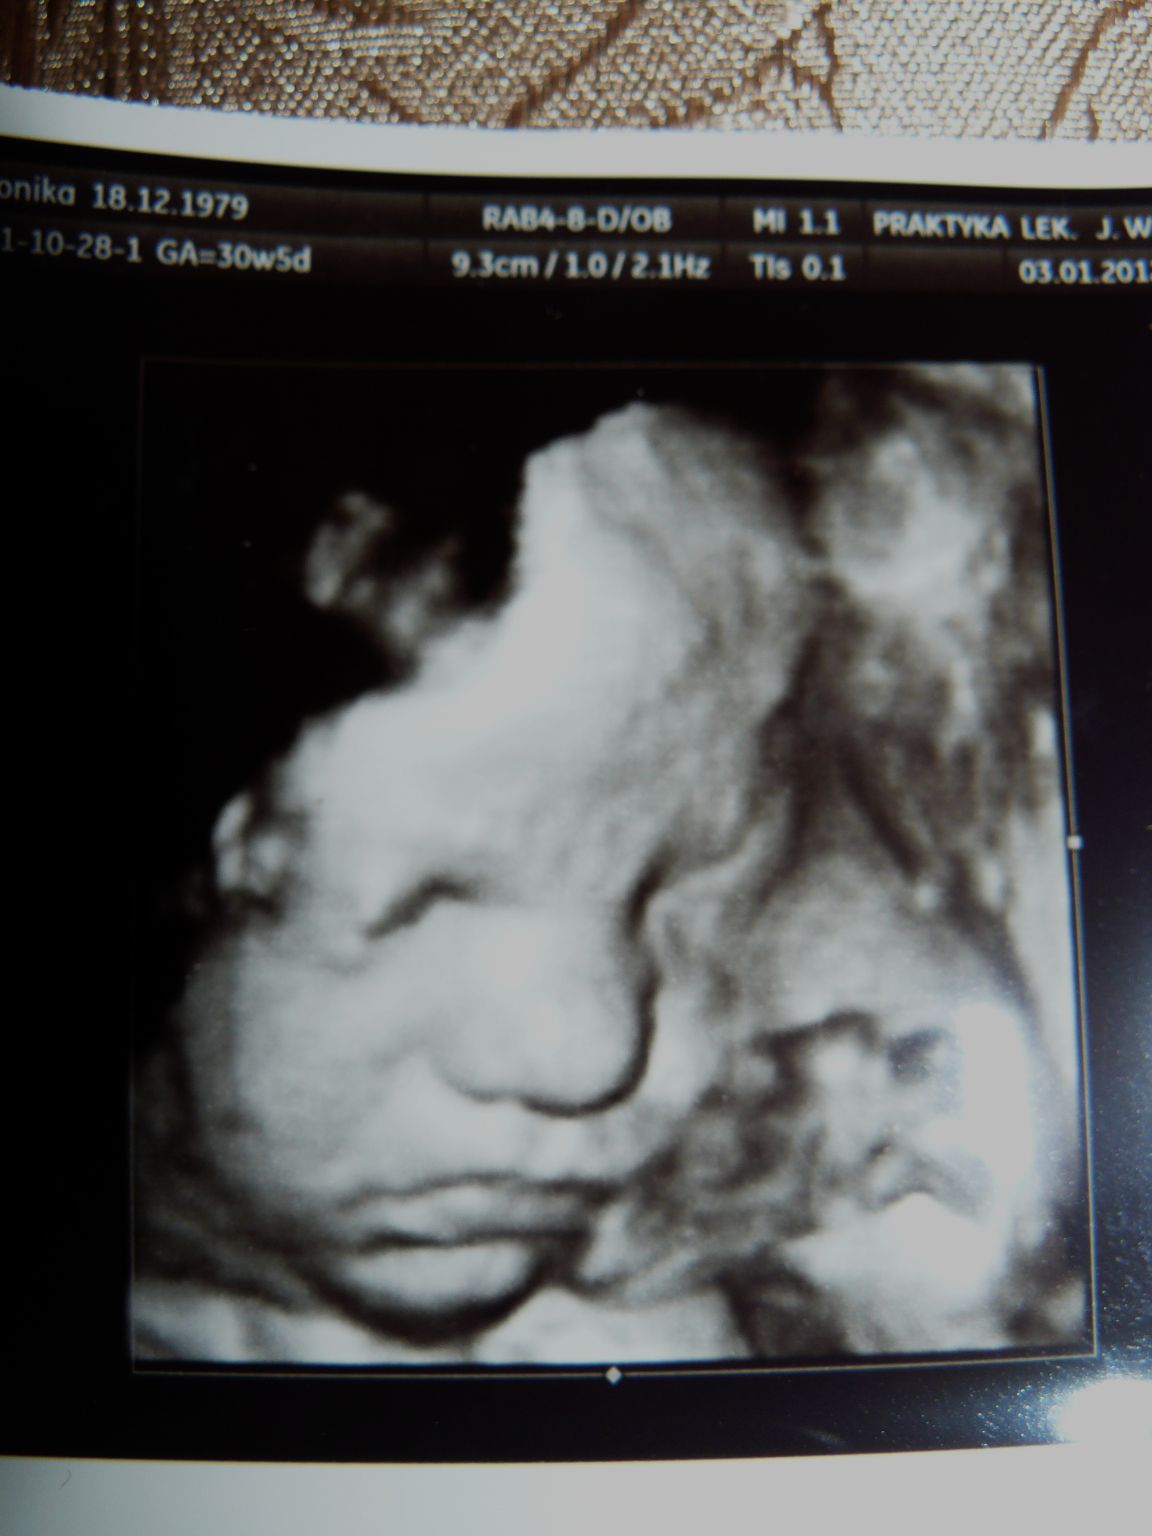

środa, 4 stycznia 2012

do kogo jest podobna?

We wtorek przyjechaliśmy do Gdańska rozentuzjazmowani nowymi zdjęciami Julci...

już w 22 tc były widoczne pewne podobieństwa do mnie, ale teraz jak zerknęliśmy na zdjęcie było to bardziej oczywiste ...

podczas badania u lekarza wyrwało mi się: "ale dlaczego ma taki garbaty nosek" po czym Julcia strzeliła focha i odwróciła się tak, że nie było jej widać...

stan fascynacji trwał do środy ... nagle coś co jest jedynie odległym planem staje się coraz bliższe, bardziej realne ... zaczęłam grzebać w zdjęciach, szukać podobieństw i efekt widoczny jest powyżej